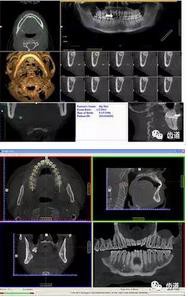

一)牙體牙髓病科

CBCT在牙體牙髓病科治療中,對牙根周圍的解剖關(guān)系、炎癥病變、囊腫等就能夠輕而易舉的進行診斷。甚至與牙齒內(nèi)根管的數(shù)目、走向、分支等都能夠通過牙科CT進行展示,使臨床醫(yī)生的根管治療不再是完全憑手感的“經(jīng)驗科學(xué)”。通過CBCT,還可以對一些“久治不愈“的疑難病例進行檢查和診斷,例如根縱列的診斷、根管內(nèi)異物的定位等,找準(zhǔn)了原因,結(jié)合先進的治療技術(shù)因病施治,使疑難病例的治療變的輕松起來。

1、牙髓根管治療

1)根管治療中牙膠尖充填在CBCT中的影像

2)根管測量

2、多生牙

多生牙的定位

二)牙槽骨外科

CBCT在牙槽骨外科手術(shù)中,通過立體影像可以全面了解牙齒周圍的解剖結(jié)構(gòu),牙根的位置,下頜神經(jīng)管的走向和范圍,上頜竇底的位置及上下牙牙根與上頜竇的關(guān)系,下牙牙根與下頜神經(jīng)管的位置關(guān)系,手術(shù)時就會“有的放失”,采用更加安全的方法,避免損傷上頜竇和下牙槽神經(jīng)。

1、上頜尖牙阻生

上頜尖牙埋伏阻生在CBCT中的影像

2、下頜磨牙阻生

下頜第二第三磨牙阻生口腔曲面斷層片影像

下頜第二第三磨牙阻生CBCT影像定位

三種圖片的影像學(xué)比較

1、下頜骨種植牙前測量準(zhǔn)備影像

2、上頜骨種植牙前準(zhǔn)備影像

3、下頜骨種植牙術(shù)后